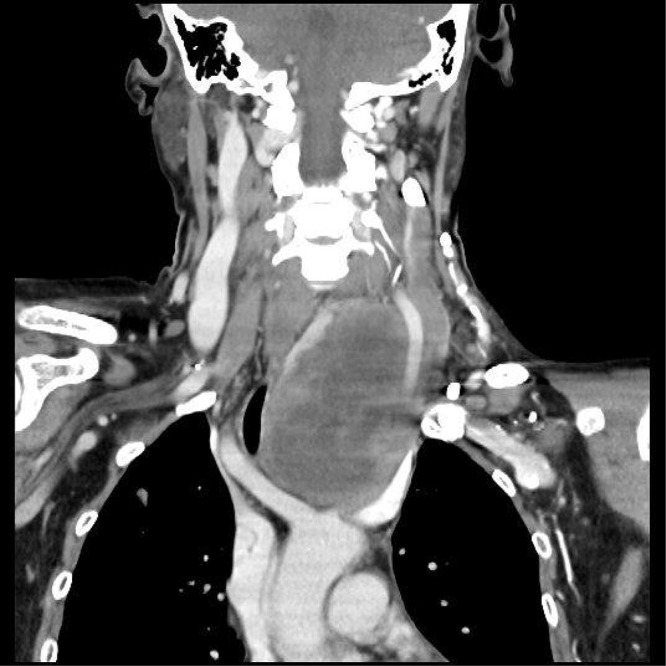

Case presentation: A 55-year-old female with no prior thyroid disease was diagnosed with advanced ATC after a routine check-up revealed a neck mass. She presented with a tumor compressing the trachea, recurrent laryngeal nerve, and carotid sinus, accompanied by Horner's syndrome. Fine-needle aspiration confirmed anaplastic sarcoma. After a multidisciplinary consultation, the patient was treated with anlotinib, tislelizumab, and albumin-bound paclitaxel, resulting in significant tumor shrinkage and symptomatic relief. However, due to financial constraints, treatment was discontinued. One month later, the tumor rapidly progressed, leading to tracheal compression and asphyxiation, causing her death.